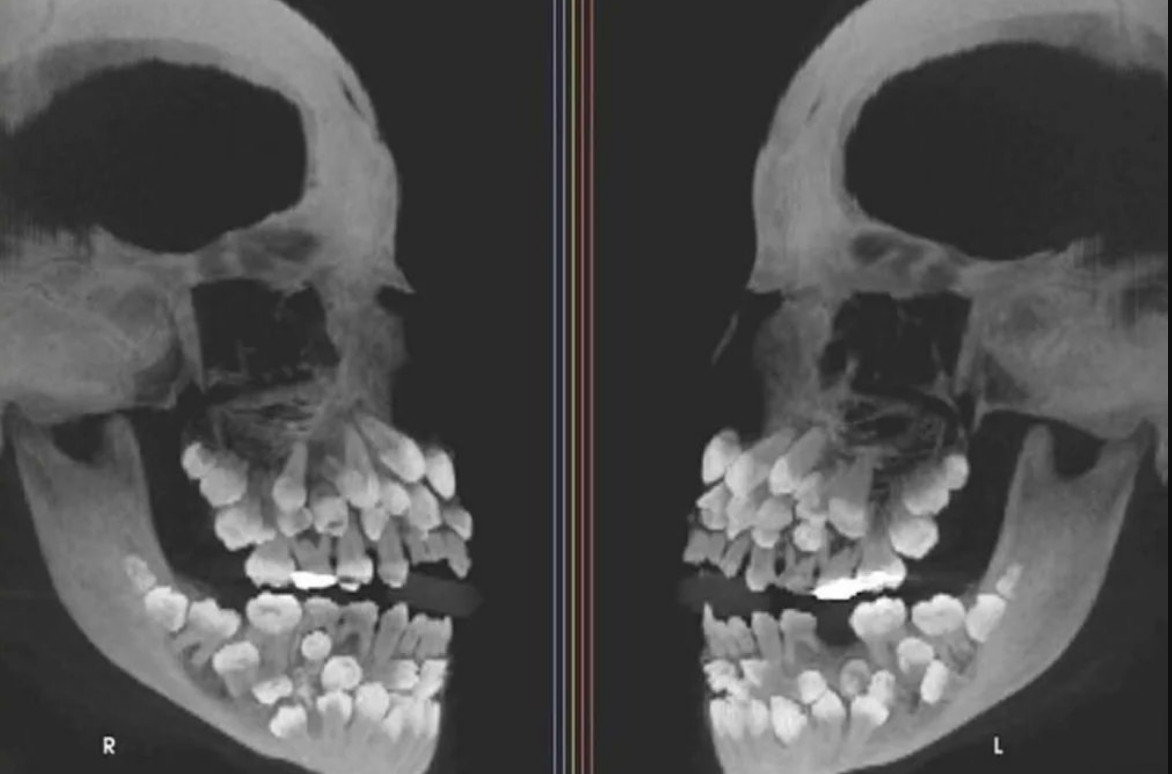

綜合外媒報導,巴西米納斯吉拉斯州一名女童因計畫拔除一顆上排乳牙,接受牙科檢查,然而,X光影像揭示驚人發現,她嘴中竟然有18顆乳牙、32顆恆牙,以及額外的31顆多生牙,牙齒總數高達81顆。

正常成年人應有32顆牙齒,而額外多長出來的牙齒則被定義為「多生牙」,一般多生牙只會出現1到2顆,因此像該名巴西女童如此數量驚人的多生牙極為罕見。多生牙常深藏牙齦,不只會阻礙正常牙齒生長,導致牙齒排列不齊,甚至引發囊腫等問題。

巴西胡伊斯迪福拉聯邦大學牙科醫院研究團隊,將這起罕見病例發表在美國《牙齒矯正與口腔顎面外科學會雜誌》上,研究人員利用精密影像定位牙齒,並進行基因檢測,想探究是否有遺傳疾病因素。經由染色體檢查發現巴西女童有罕見遺傳變異,但與多生牙的直接因果關係目前仍待進一步釐清。

由於部分多生牙深埋在牙齦中,或者外觀與正常牙齒難以區分,如果隨意拔除,可能會傷到顎骨。為此,研究團隊找來了矯正科、口腔外科、牙周病科和假牙科等多位專家,一起商討並制定了長期的治療方案,就是希望可以好好保護她的牙齒健康,維護她日後牙齒可以排列整齊。